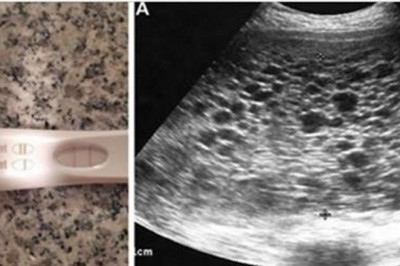

Sprawdzając test ciążowy bardzo się cieszy! Podczas USG lekarz zamiast dziecka dostrzega setki

Pewna para była starała się o drugie dziecko i gdy kobieta zrobiła test ciążowy Nie mogła powstrzymać radości.